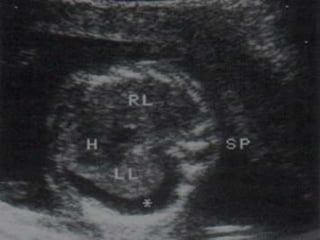

HALLAZGOS ECOGRÁFICOS: ASCITIS,

DERRAME PLEURAL, EDEMA SUBCUTÁNEO,

EDEMA PLACENTARIO.